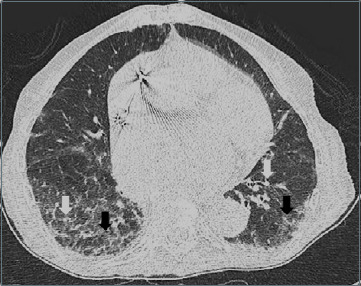

Radiographic pulmonary description of bilateral multifocal patchy with ground-glass opacifications needs careful evaluation in the Era of SARS-CoV-2

J. Gerontol. Geriatr. 2022, 70(1), 83-85; https://doi.org/10.36150/2499-6564-N324 - 28 Sep 2021

In the COVID-19 Era, multilobe ground-glass opacities (GGOs) and septal thickening on chest Computed Tomography (CT) have been recognized as a radiological finding highly suggestive for SARS-CoV-2 pneumonia. However, these findings can be misleading. Here, we report about an 81-year-old woman, evaluated in [...] Read more.

In the COVID-19 Era, multilobe ground-glass opacities (GGOs) and septal thickening on chest Computed Tomography (CT) have been recognized as a radiological finding highly suggestive for SARS-CoV-2 pneumonia. However, these findings can be misleading. Here, we report about an 81-year-old woman, evaluated in the Emergency Room (ER) for a traumatic hip fracture, who, despite negative molecular testing on the nasopharyngeal sample for SARS-CoV-2, was admitted to a COVID-Unit because of flu-like symptoms with GGOs and interlobular septal thickening on the chest CT. During the hospital stay, focusing on the patient’s medical history, the interstitial lung disease was defined to be a chronic complication of long-term use of Amiodarone and rheumatoid arthritis. Therefore, especially during SARS global pandemic, CT pathological findings suggestive for interstitial pneumopathy should be critically analyzed considering patient history. They can reflect, in fact, other pathological conditions different from SARS-CoV-2 infection as other viral and non-viral infections or chronic inflammatory diseases. Full article